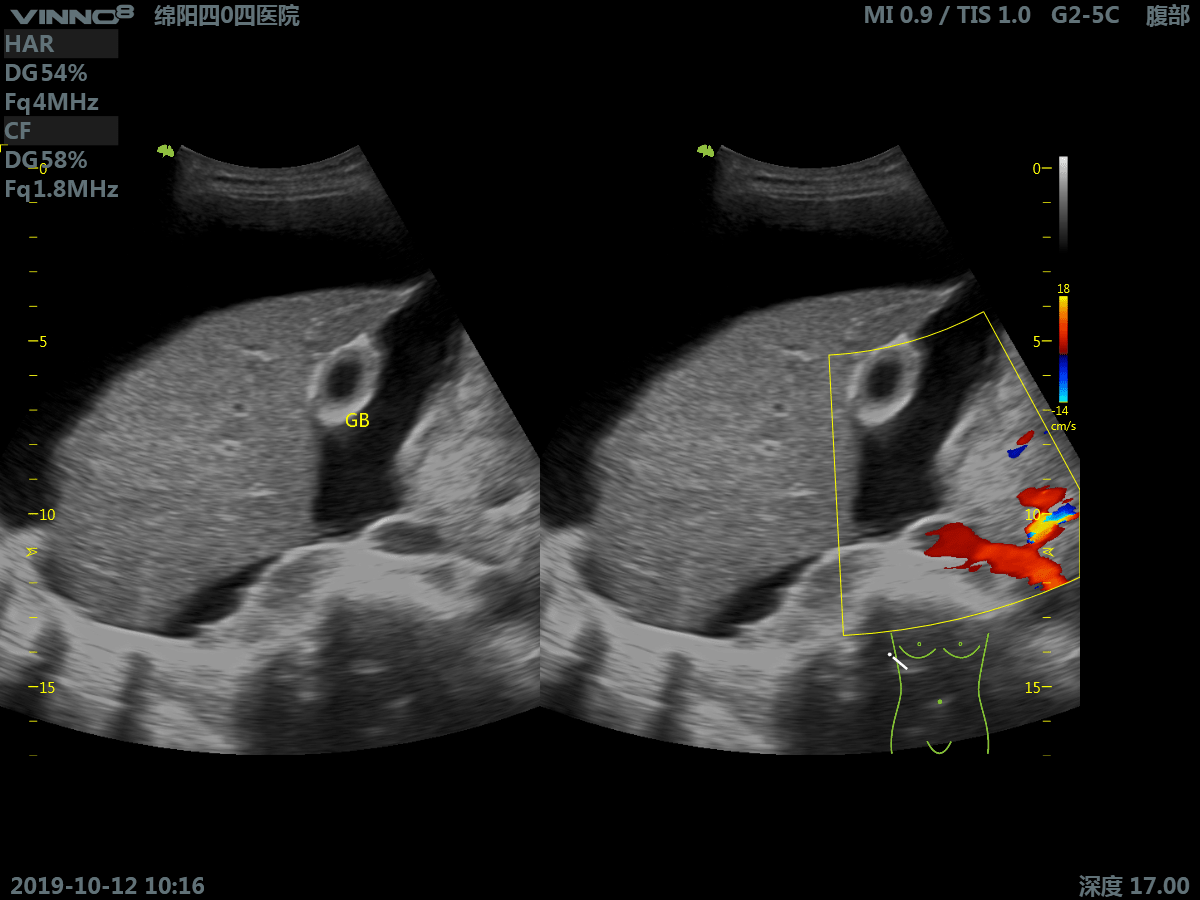

10. CFM. Режим цветового допплера

11. CFM+B (B+CF). Комбинированный режим: цветовое допплеровское картирование + В режим

- брюшная полость

- периферические сосуды